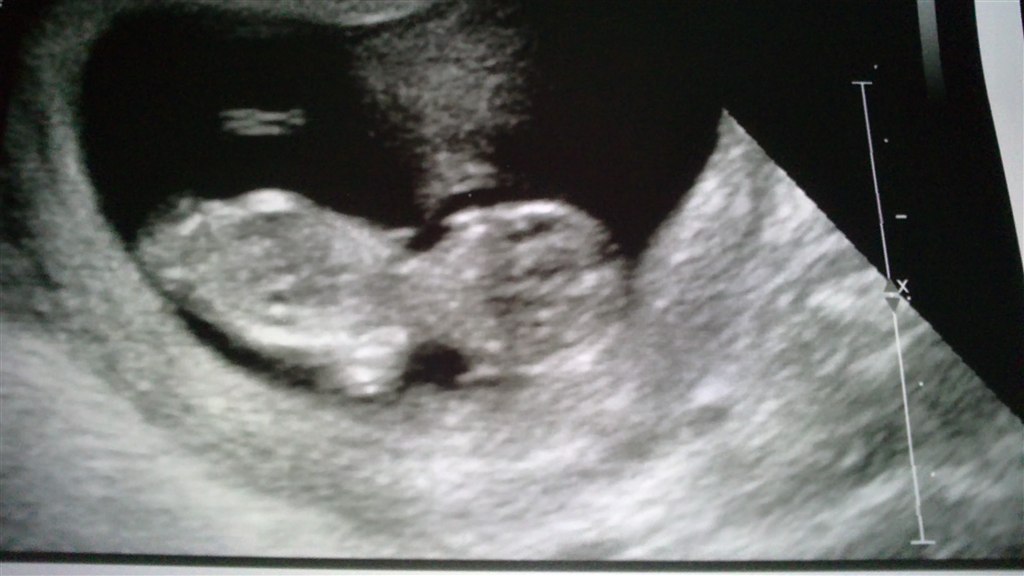

Vi var til nakkefoldsscanning igår, og det var dejligt og sjovt at se haletudsen, der hoppede rundt som var det en bedre hoppeborg og ville ikke ligge stille så de kunne måle den. Da så den endelig faldt til ro skulle den lige være på tværs igen og lægge sig til at sove med hovedet ud mod mit maveskind og benene indad, så den stadig ikke kunne måles!

og mine stakkels tarme. Tilsidst måtte de ty til at scanne op gennem skeden og fik heldig vis der en vinkel på haletudsen så den kunne måles fra hoved til hale, 6,2cm lang og ca det samme i ben

. Men vi fik aldrig et ordenligt billede af den, vi fik det mindst dårlige med hjem. (det ligner mest af alt et fyldt 8 tal

) forhåbentlig er vi mere heldige med vores aktive og stædige frø næste gang. Jordmoderen som scannede mig sagde også at det ikke ville gøre så ondt næste gang, da min livmoder der ville være vokset meget.